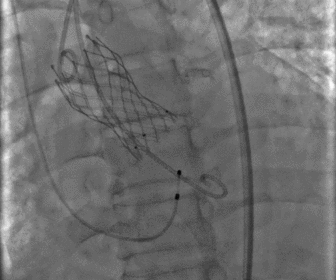

术中影像

图片

左冠造影

左冠球扩

左冠支架植入

瓣膜释放完毕

术后造影及超声探查未见瓣周漏,跨瓣压差术前54mmHg,术后降为0mmHg,术中及术后未出现相关并发症,手术圆满完成。